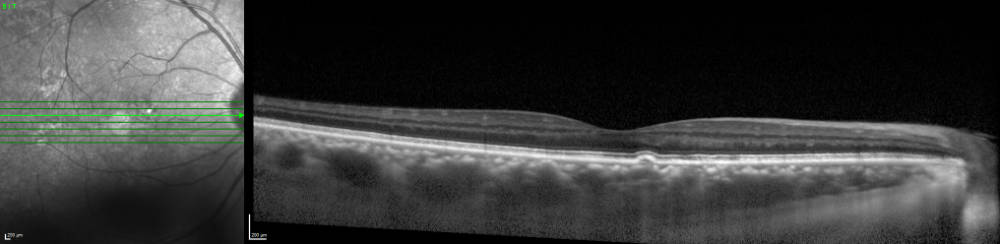

Discovery of Outer Retinal Tubulation with OCT

Zweifel SA, Engelbert M, Laud K, Margolis R, Spaide RF, Freund KB. Outer retinal tubulation: a novel optical coherence tomography finding. Arch Ophthalmol. 2009;127:1596-602.

The Clinical Nature and Signficance of SubretinalDrusenoid Deposits or Reticular Pseudo Drusen as a manifestation of Age-Related Macular Degneration

The identification of subretinaldrusenoid deposits or reticular pseudo drusen was described in a paper on its nature and imaging characteristics. This is a major form of age-related macular degeneration.

Zweifel SA, Spaide RF, Yannuzzi LA. Acquired vitelliform detachment in patients with sub retinal

drusenoid deposit (reticular pseudodrusen). RETINA 31(2):229-34, 2011.